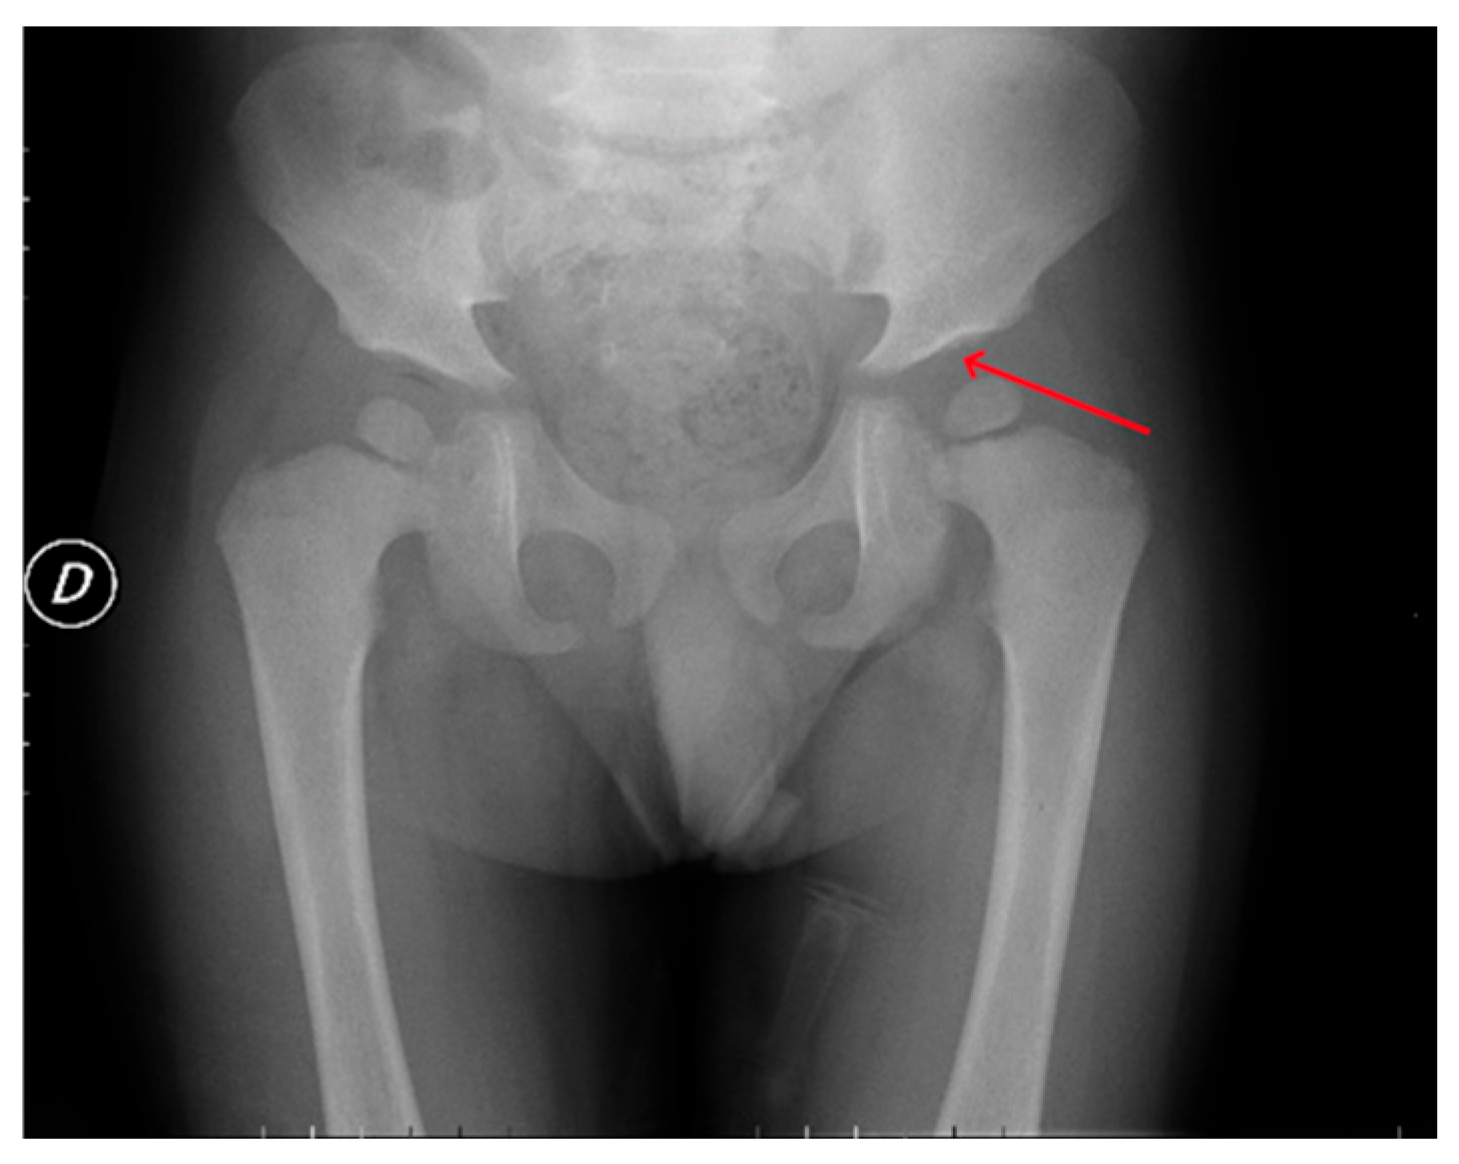

| Hip dysplasia | + | + | + | + | + | + | + | + |

| P1 (MPSI) | Baseline | RX | Pelvis | Mild iliac wing hypoplasia; shifty acetabular roofs. |

| After 3 years of ERT | RX | Pelvis | Thickening of the acetabular roofs. | |